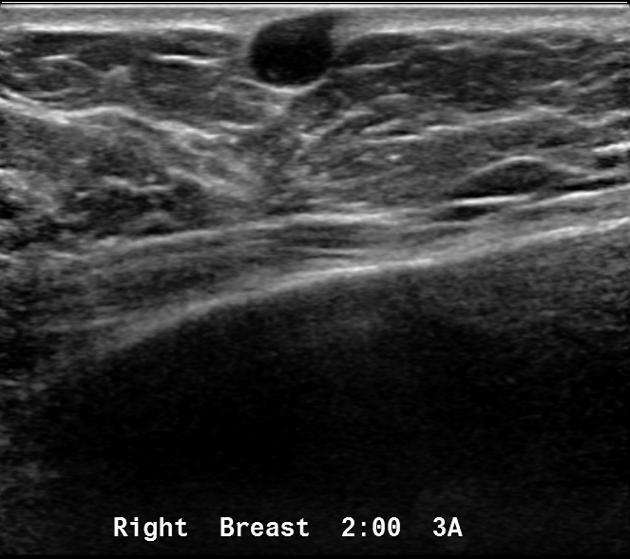

What is a Sebaceous Cyst?

benign breast condition

Superficial, sebum containing, results from obstructed sebaceous gland

What is the Sonographic Appearance of Sebaceous Cyst?

Small

Hypoechoic

Close to the skin surface

Through transmission

No detectable vascular flow

Hypo- and hyperechoic alternating rings

A characteristic track may be seen extending into the skin surface

What are the presentations of Sebaceous Cyst?

breast lump